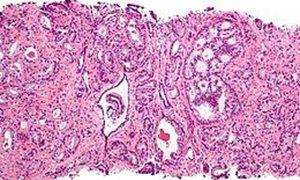

Prostaatkanker is de meest voorkomende vorm van kanker bij mannen. Jaarlijks krijgen meer dan 10.000 mannen deze ziekte en overlijden er 2.500 aan. De invoering van bevolkingsonderzoek naar prostaatkanker kan deze sterfte met zeker 22 procent verminderen. De huidige praktijk is om de mogelijke aanwezigheid van prostaatkanker vast te stellen op basis van verhoogde PSA-waarden in het bloed en vervolgens een prostaatbiopt. Deze methode wijst echter ook relatief onschuldige prostaatproblemen aan en leidt tot veel (over)diagnose en overbehandeling. Daarom is deze techniek niet geschikt voor bevolkingsonderzoek.